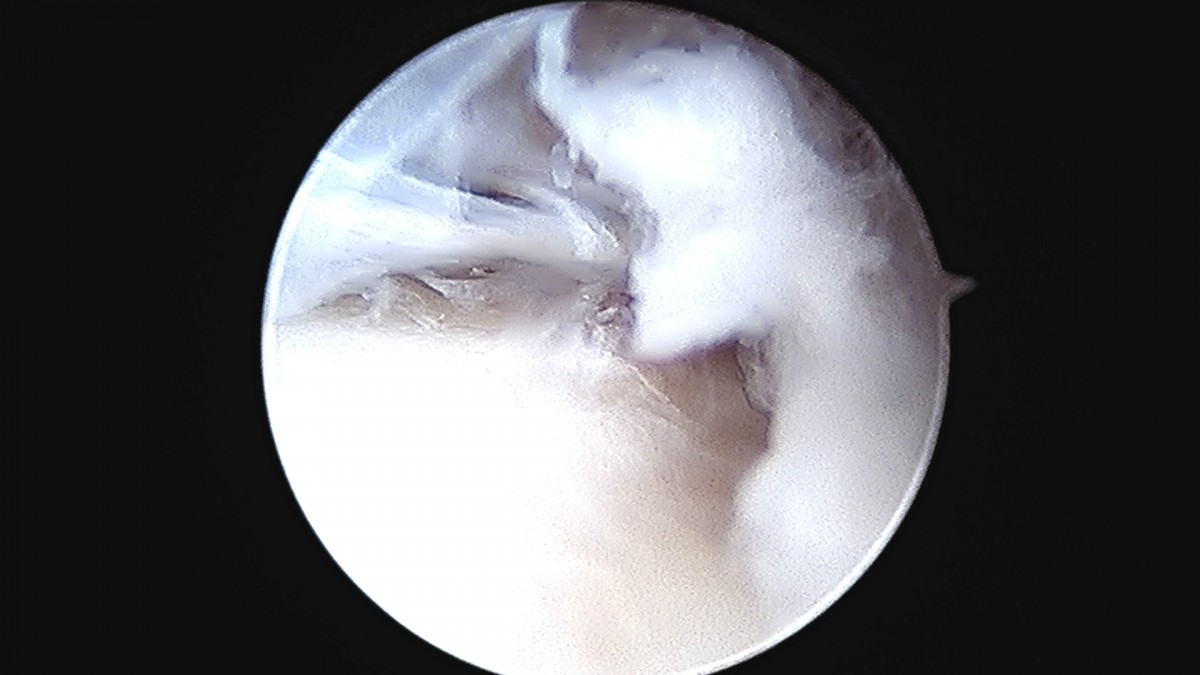

정지영원장님 발목 변연절제술 권공O 환자

dae765e4d9ac96aee867c9d6292d8784_1758009856_2739.jpg